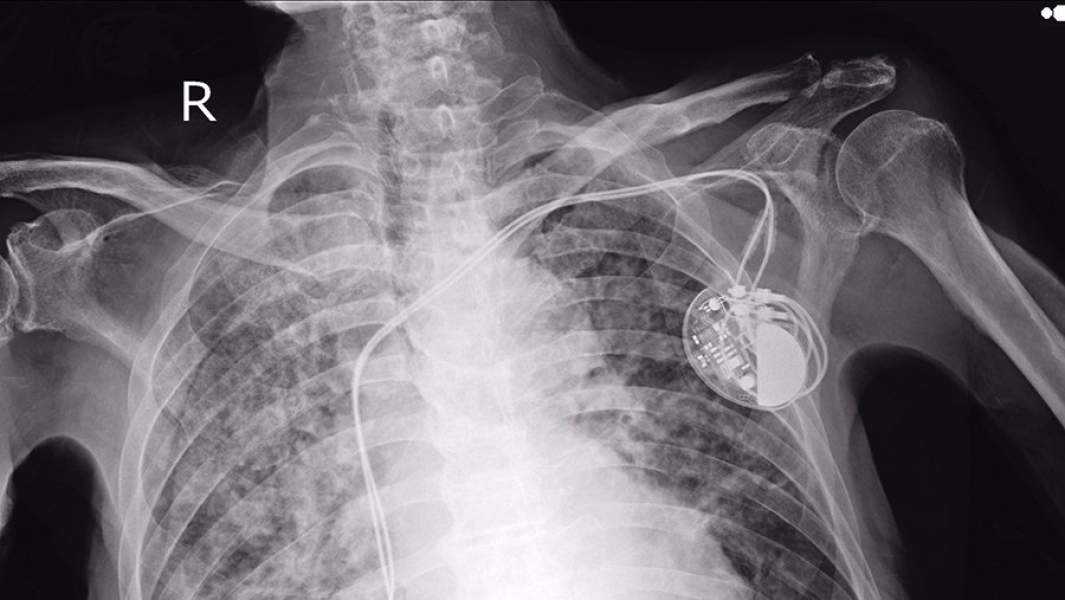

Кардиостимулятор — это прибор, который вживляется под кожу и включает внутрисосудистое вмешательство. Его устанавливают, когда сердце человека сокращается с очень низкой частотой. Пациентам, которые носят кардиостимулятор, противопоказано делать магнитно-резонансную томографию и находиться рядом с линиями электропередач.

— Если раньше это было здоровенное устройство в половину мобильного телефона, которое создавало частоту, то сейчас это небольшой, но очень мощный компьютер размером где-то 3x3 см и толщиной меньше 1 см. Он анализирует ЭКГ и по требованию включается, если частота пульса падает ниже указанных значений. Кардиостимулятор — очень умный прибор. Он анализирует не только то, с какой частотой ему нужно работать, но и то, с какой частотой это нужно человеку. То есть колебания прибора зависят от физической нагрузки: человек пошел побыстрее или побежал, соответственно он увеличивает частоту, — отметил Беленков.

С развитием технологий кардиостимуляторы стали еще умнее: когда у пациентов возникает жизнеугрожающее нарушение ритма сердца, требующую дефибрилляции желудочков, этот маленький прибор может спасти человеку жизнь.

— По сути, этот небольшой аппарат делает весь цикл мероприятий, которые нам часто показывают в кино. Когда человек упал, к нему бежит врач с огромным прибором, зачем-то стучит друг о друга электроды и прикладывает человеку к грудной клетке. Всё это способен сделать маленький кардиостимулятор: он анализирует информацию, распознает нарушение и заводит сердце. Программы, заложенные в нем, регулируются магнитным полем. За счет электромагнитных волн к нему прикладывается программатор и задает программу работы, — резюмировал доктор медицинских наук.